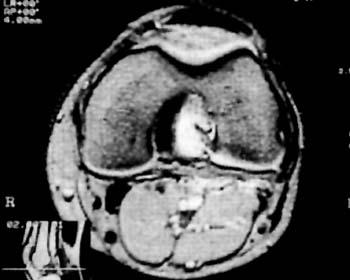

Los estudios Rx, y de TAC fueron en todos los casos negativos, en cambio, se destaca la RNM como metodo fundamental para su diagnostico. (Fig 1)

El mismo se caracteriza por su ubicacion central adosado al Ligamento Cruzado Posterior desplazando hacia lateral al Ligamento Cruzado Anterior.

Su densidad lo asemeja como un tumor con caracteristicas liquidas y su forma multilobulada ocupa practicamente el intercondilo femoral (Fig 2-3-4) En T2 es facilmente distinguible como una masa homogenea que ocupa todo el contorno del condilo femoral interno.